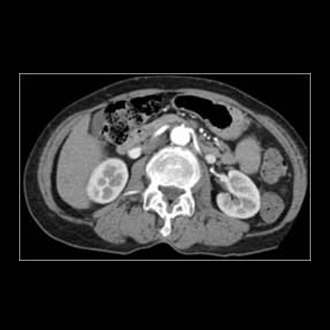

A CT scan is an x-ray procedure that is enhanced by a computer and gives out a three-dimensional view (referred to as a “slice”) of a particular part of the body.

While dense tissue can block some areas during standard x-ray image procedures, CT scans create a three-dimensional view by using a computer to combine different slices, showing all bone and tissue.